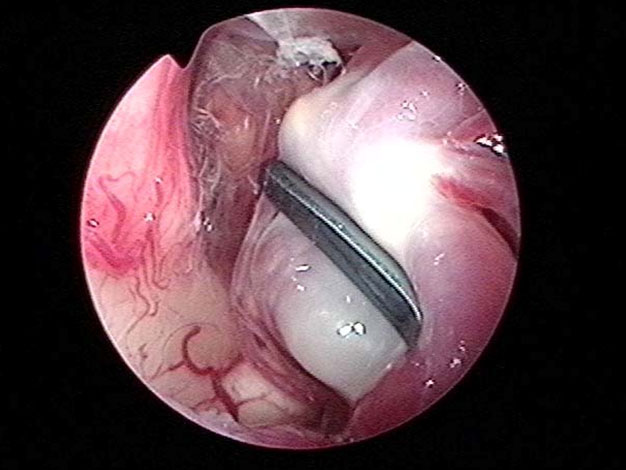

神経内視鏡による同時観察下で顕微鏡手術(図4)。

神経内視鏡は顕微鏡の死角を補い、動脈瘤周囲の細い血管を温存することに非常に有用です(図5、6)。この方法は当科において確立され、現在では動脈瘤手術において実に有用で必要な方法として認められています。